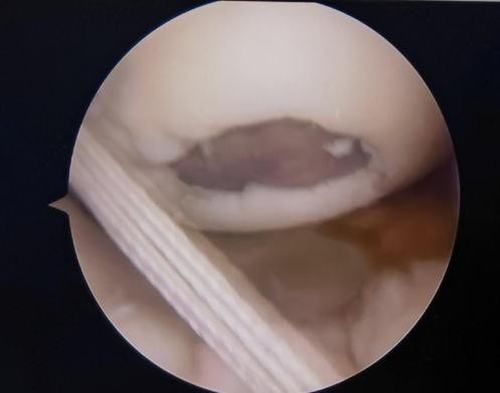

鏡下重建前交叉韌帶走形、張力良好

經患者同意后,李鵬主任手術團隊制定詳細手術方案。手術如期進行,經團隊密切配合,對幾位患者分別順利完成關節鏡下膝關節鏡鏡檢、關節清理、股薄肌半腱肌取腱移植術、前交叉韌帶重建術、軟骨損傷微骨折術、半月板縫合修整術等。